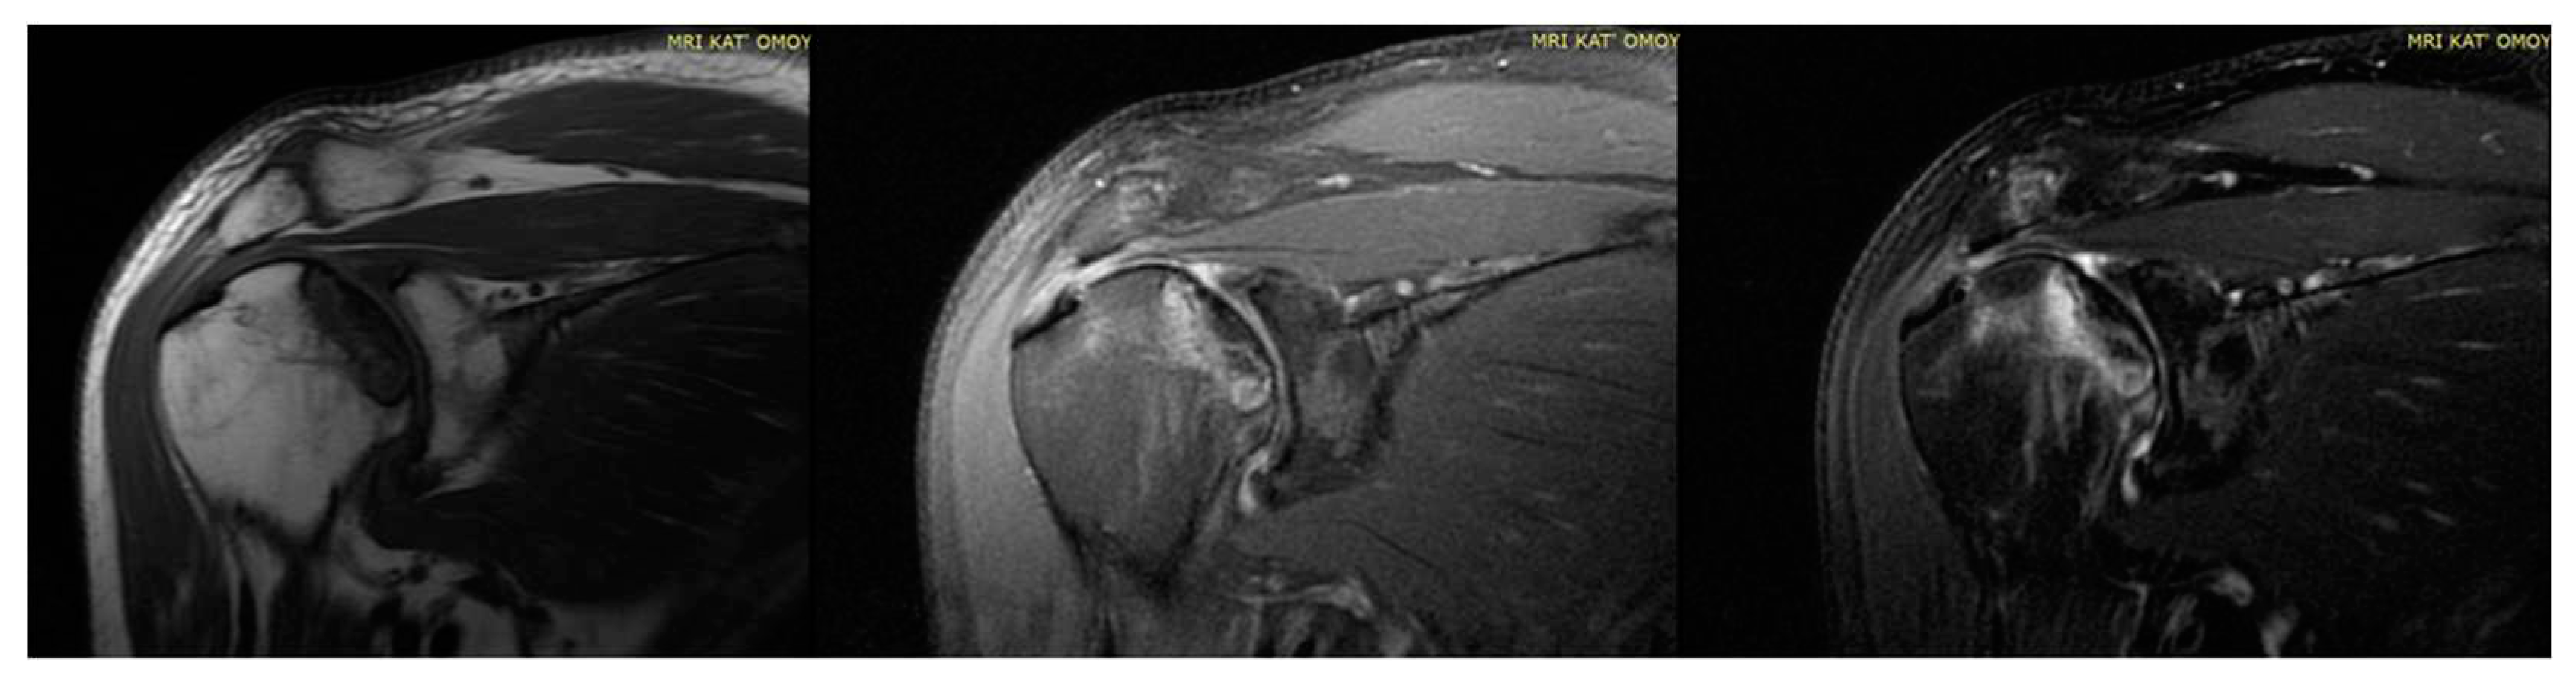

Figure 3. MRI of bilateral AVN of humerus head (left).